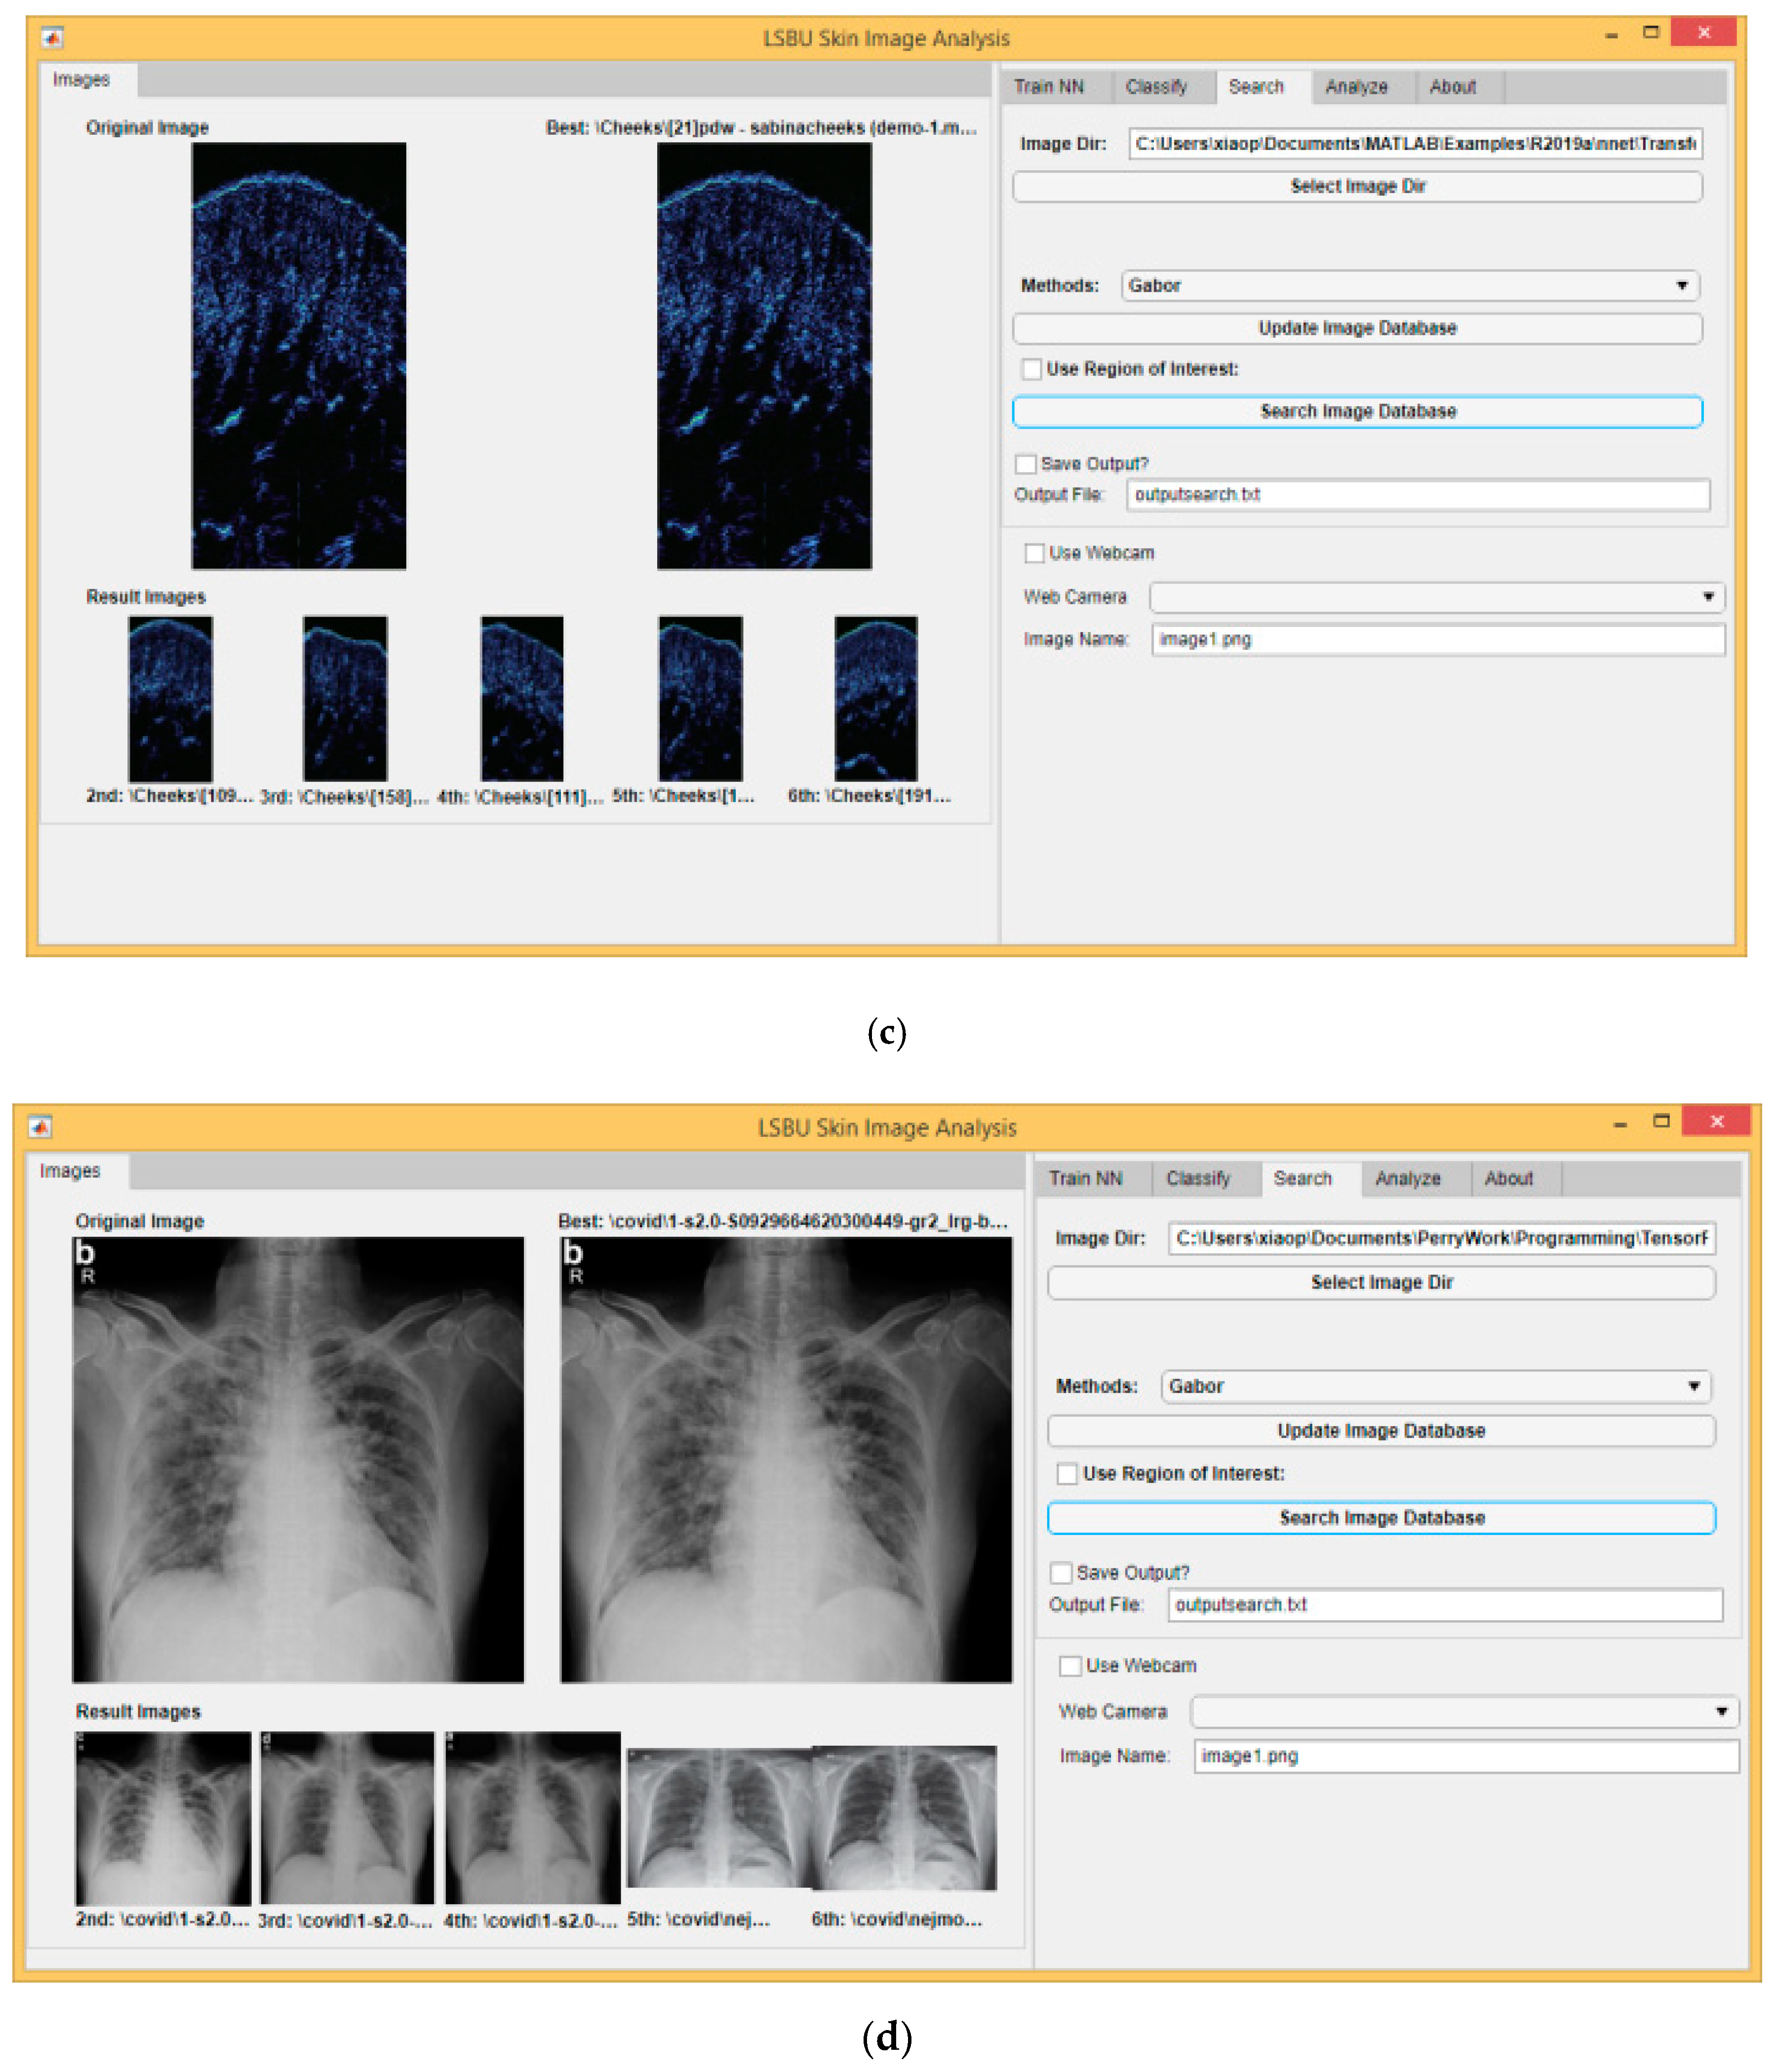

Another useful usage of skin texture analysis is image retrieval or image searching. This is particularly suitable for skin images, where similarities are much higher than normal images. Figure 6a shows the skin cancer image searching results using Gabor wavelet transform. As we use the same image database for training and searching, the best matching result is the query image itself. The second to sixth best matching results are also from the same category of the query image, i.e., benign images. Figure 6b–d show the image searching results using Gabor wavelet transform on skin capacitive images, skin ultrasound images and chest X-ray images. Similar to Figure 6a, all the best matching results are from the same category of the query image.

Figure 6.

Image searching results using Gabor wavelet transform on different type of images. (a) skin capacitive images; (b) skin cancer images; (c) skin ultrasound images; (d) chest X-ray images.